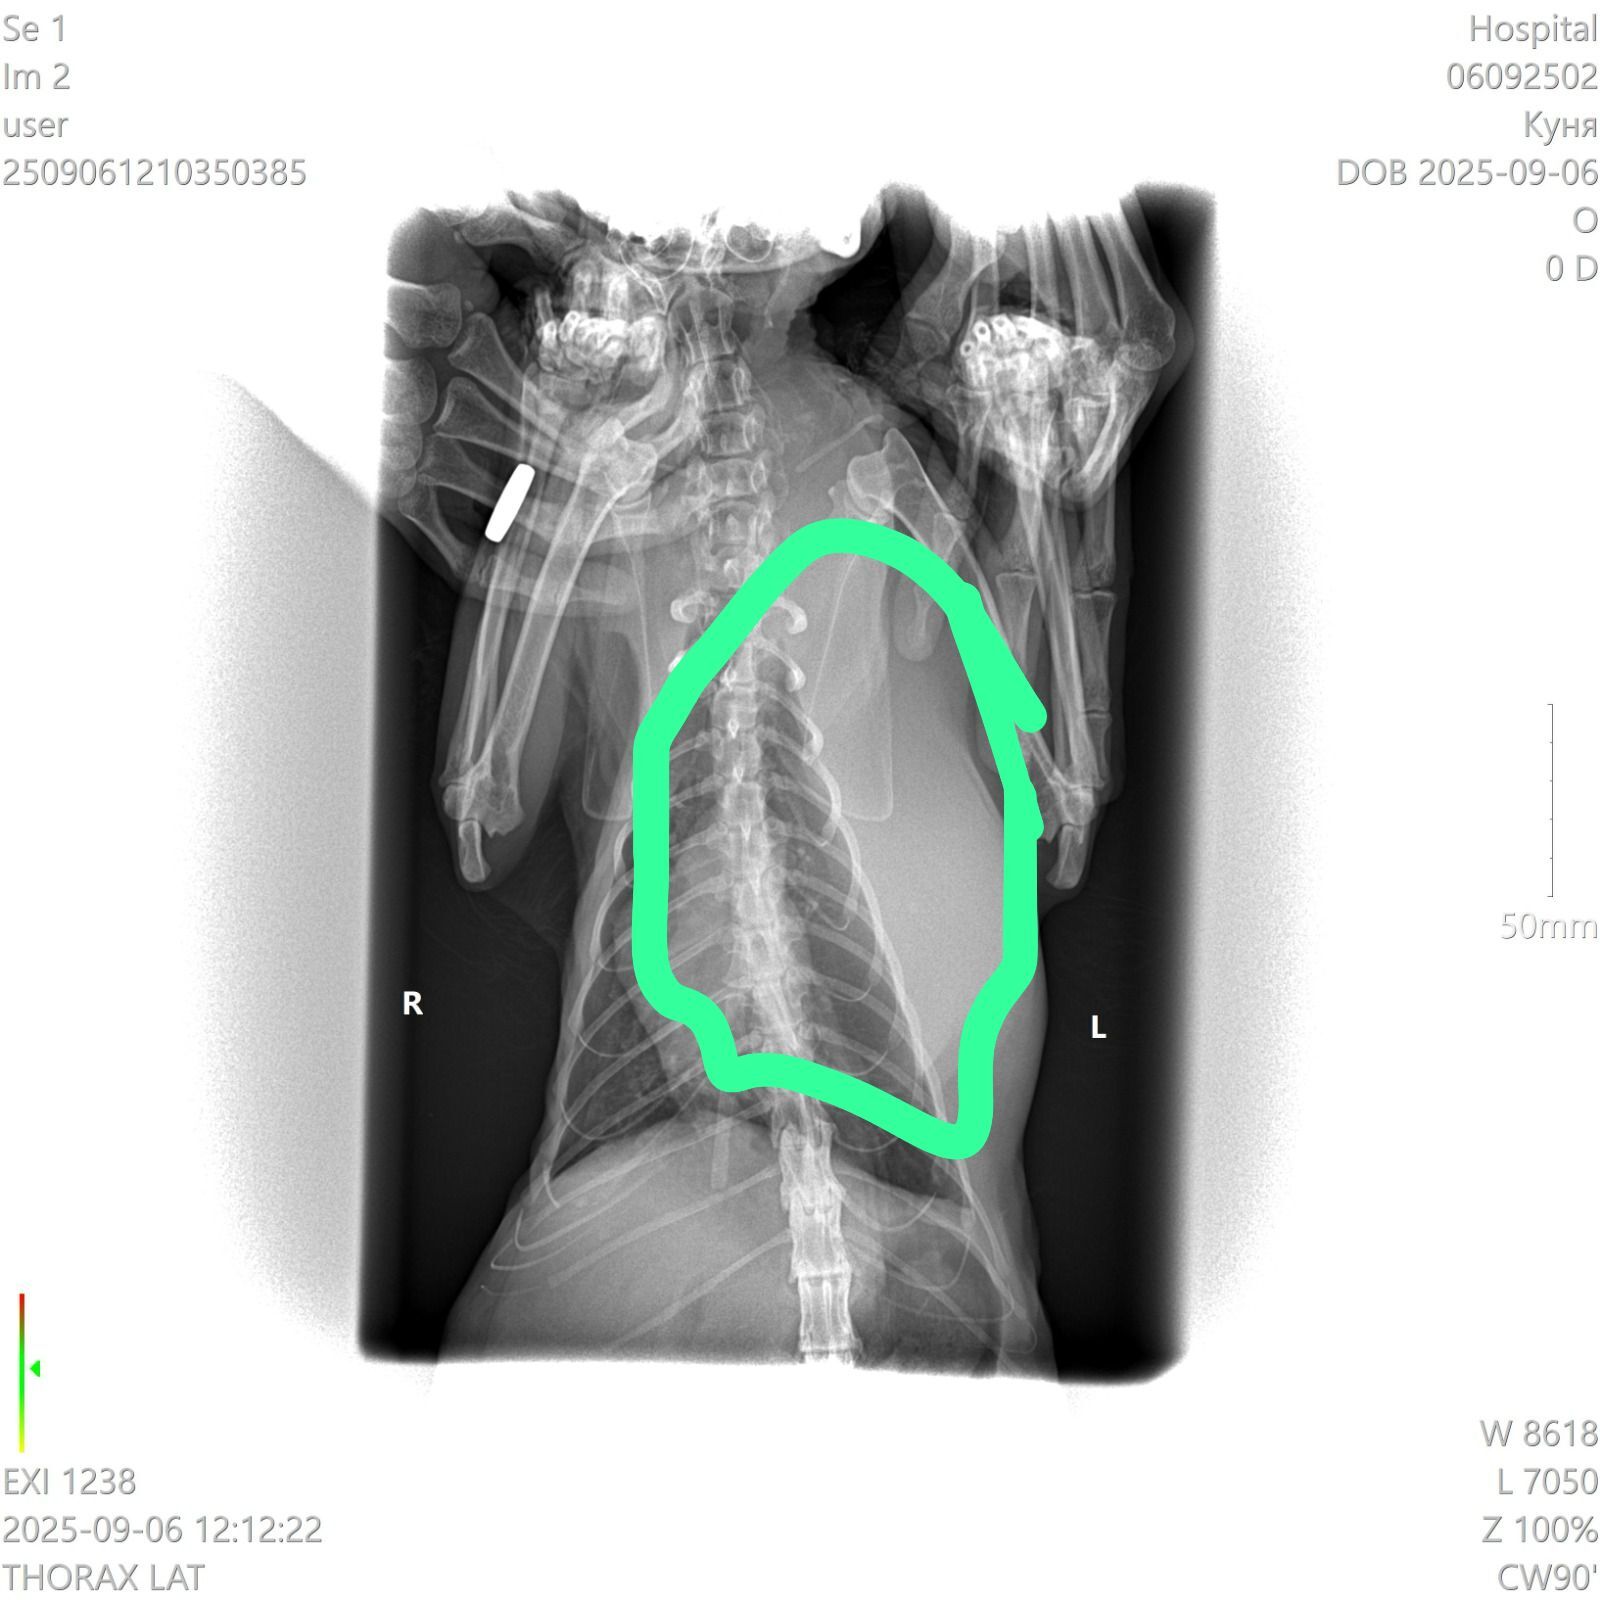

У кошки опухла левая часть грудной клетки.

Сделали рентген. Сказали что это не легкие, а какое-то новообразование. Что это может быть? У кошки тяжелое дыхание, почти не ест и не пьёт, приходится кормить через силу.